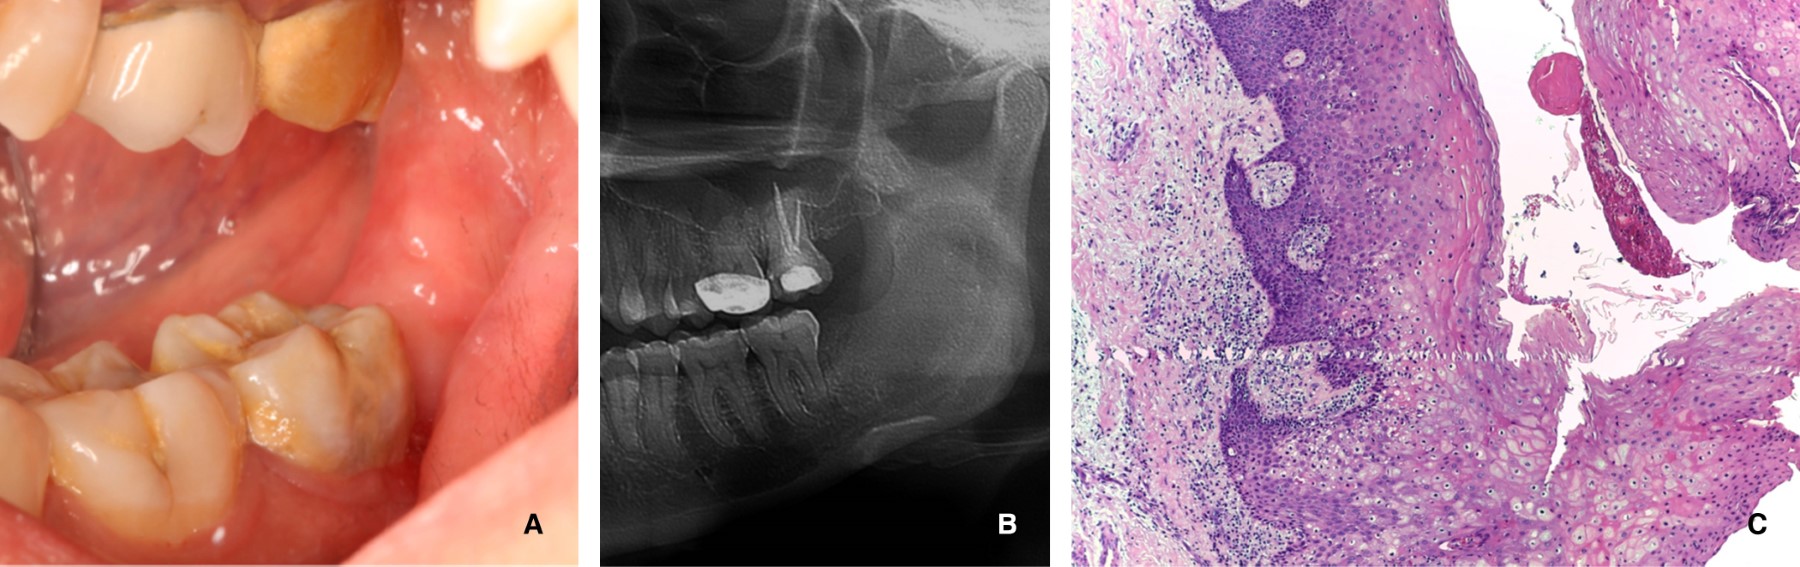

La Figura 3 A y B muestra clínica y radiográficamente el área de la lesión después de la segunda cirugía. No existe recurrencia después de 28 meses, y se ha programado el seguimiento clínico y radiográfico a largo plazo. Aunque la paciente no presentaba macrocefalia, por su edad y tamaño de la lesión, fue examinada en busca de anormalidades esqueletales en el cráneo, y la presencia de depresiones en las palmas de las manos y las plantas de los pies. No se encontró ningún síntoma que pudiera asociarse con el síndrome de carcinoma de células basales nevoide.

Histológicamente se observó un fragmento de tejido blando compuesto de epitelio con metaplasia escamosa, rodeado por una cápsula de tejido conjuntivo fibroso denso, bien vascularizado y un moderado infiltrado inflamatorio de predominio linfocitario. Además, en el tejido conjuntivo adyacente a la lesión se encontró tejido mineralizado compatible con cemento, haces de tejido muscular de tipo estriado esquelético y acinos glandulares mucoserosos. Finalmente, se emitió el diagnóstico de queratoquiste odontogénico con metaplasia escamosa (Figura 3C).